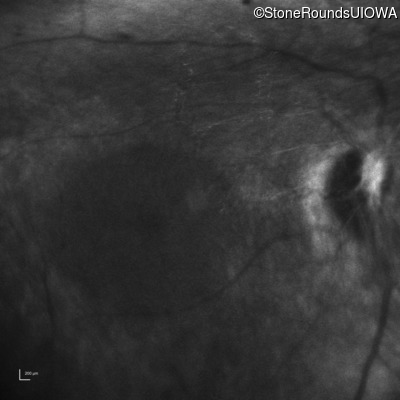

Infrared Fundus Photograph - Left - No Light Perception

Exemplar